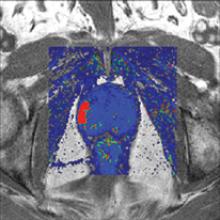

Treatment planning is a critical component of a patient’s road toward an optimal outcome when dealing with cancer. Whether the ultimate goal is palliative or a total cure, treatment planning always aims to provide just enough dose to a targeted area to eradicate the cancer, while sparing nearby tissue or organs.